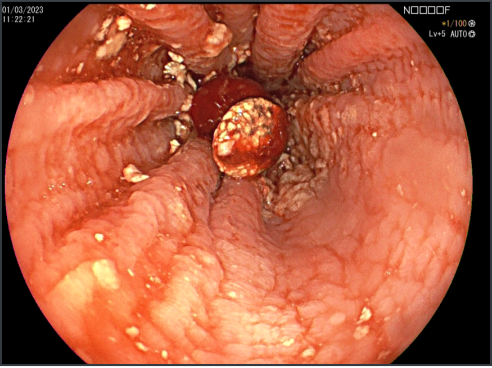

Coledocoscopía

Estudio Detallado de la Vía Biliar

Requiere de Equipamiento Especial

Permite Toma de Muestras Bajo Visión Directa de los Conductos Biliares